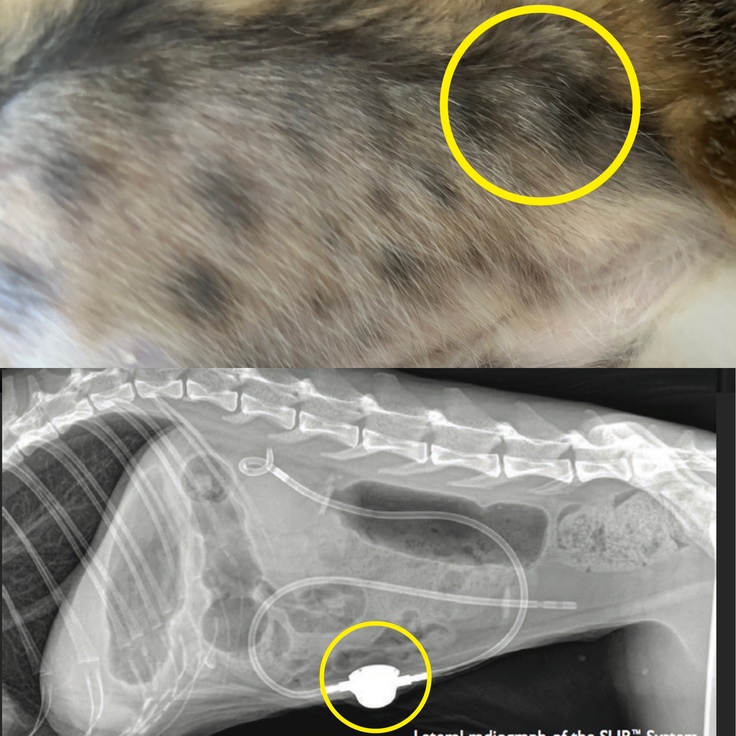

SUBシステム洗浄と検査結果。

今回洗浄するSUBシステムとは

腎臓と膀胱を繋いでいる人工インプラントです。

丸で囲っているところにポートがあり

そちらに専用の洗浄液を注射器で流します。

なぜこの洗浄が最低1ヶ月〜に1回必要かというと人工物の為自浄作用がなく結石が詰まったり汚れてしまうからです。私がこのメンテナンスがかかるSUBシステムにした理由の中には尿管に結石が詰まる度に小さなまぐのお腹にメスを入れたくないと思いもありました。

手術したまぐのお腹。少しずつ毛が生えてきました✨

本日の検査結果がこちらになります。